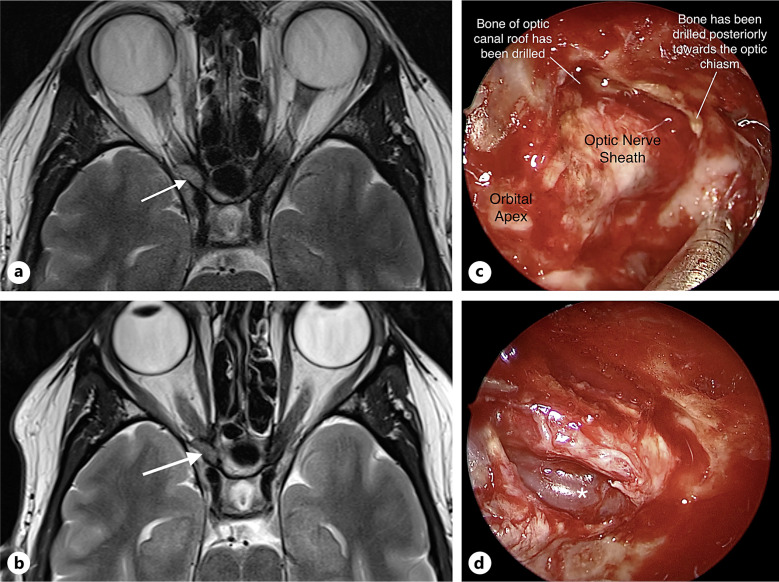

Case presentation: A 43-year-old female presented with an 18-month history of painless vision loss secondary to an intracanalicular venous malformation causing compressive optic neuropathy. Ophthalmic examination showed reduced visual acuity and color vision, relative afferent pupillary defect, and optic disc pallor. Imaging findings were consistent with a slow-flow vascular malformation. An endoscopic transsphenoidal optic canal decompression was performed. The lesion was found to be wrapping around the optic nerve. At follow-up after 1 year, visual acuity had improved along with restoration of full color vision and visual fields.